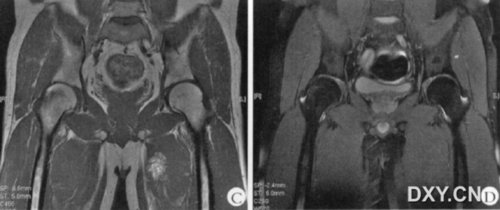

A~D:为同一患者,男性,36岁,A~C为发病时第1次MRI表现,D为3个月后MRI表现。

A:MRI轴位T2WI抑脂,右侧髋关节一过性骨髓水肿综合征,右侧股骨头、股骨颈、粗隆高信号,股骨头形态正常;

B:MRI冠状位PD抑脂,右侧髋关节一过性骨髓水肿综合征,右侧股骨头、股骨颈、粗隆高信号,股骨头形态正常;

C:MRI轴位T1WI,右侧髋关节一过性骨髓水肿综合征,右侧股骨头、股骨颈、粗隆信号稍减低,股骨头形态正常;

D:MRI冠状位PD抑脂,正常髋关节,双侧股骨头、股骨颈、粗隆信号正常。